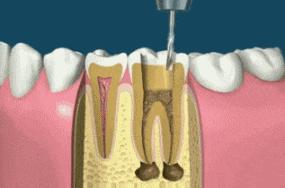

什么是根管治疗呢?所谓根管治疗,又称牙髓治疗,是治疗根尖周病或牙髓病最有效的技术。它通过清除根管内的坏死物质和发炎的牙髓,并进行适当的消毒,填充根管,以去除根管内的容物对根尖周围组织的不良刺激。根管治疗这种治疗方式不仅使牙齿得以保留,还能与拔牙术互补呢!一般牙齿因龋齿有洞,外部细菌侵入到牙髓腔,导致牙髓受到细菌感染而发炎的或是细菌侵入牙槽骨里,引起牙根尖周围组织发炎的,都需要进行根管治疗。

根管治疗也不同于过去所说的”杀神经“。在以前,如果遇上牙髓发生炎症,引发疼痛,一般会采用将牙齿钻开,使用药物将牙齿内部发炎的牙髓统统杀死,从而缓解疼痛。但随着治疗观念的全面革新和现代口腔医学技术的进步,这种老套的方法逐渐被淘汰。相比于”杀神经“,根管治疗的修复效果会更彻底,能进行更加彻底的清理和严格的消毒,并用人工的充填材料将”根管“严密填塞。

话虽如此,很多患者还是担心:根管治疗会不会非常疼啊?一般,做根管治疗前医生都会给予局部的麻醉处理。就算是打局部麻药时,也会在注射部分表面涂抹外用的麻醉剂,所以在根管治疗的过程中,几乎连注射所带来的轻微疼痛都感受不到。在治疗后的几天内,可能会出现轻微的疼痛,但这都属于正常现象,一般2到3天就能得到缓解。